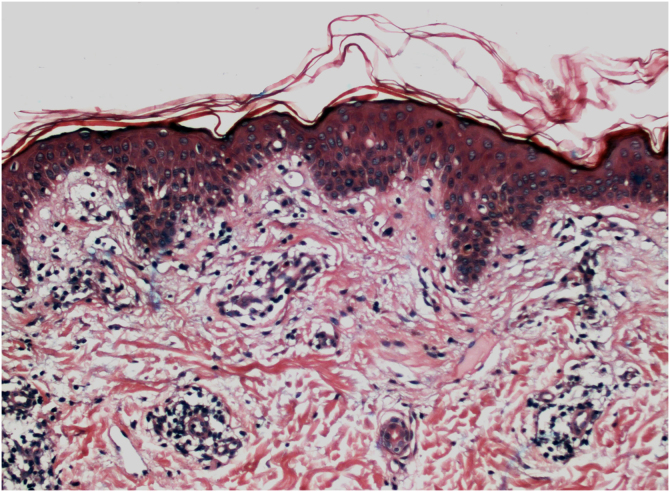

组织病理学上,多达 78% 的白癜风表皮在基底层色素沉着较少,多达 48% 的病例可发现一些炎症浸润。在活动性白癜风病例中,组织病理学可能显示苔藓样界面性皮炎模式,表明自侵的焦点位于基底层。T淋巴细胞 (CD3+),尤其是细胞毒性表型 (CD8+),是浸润物中的主要细胞 (65.4%),在血管周围和附件周围分布的病灶周围皮肤中更为明显。因此,病灶周围皮肤被认为是白癜风炎症活动性最高的区域(图1,图 2)

图 2:活动性白癜风。组织病理学:血管周围淋巴细胞浸润,表皮侵袭和基底层空泡变性灶(苏木精和伊红,×40)。